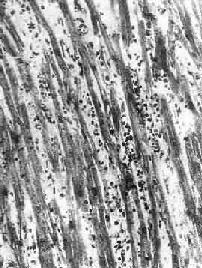

本病病变依患者年龄不同而有所不同。妊娠最初3个月的胎儿感染风疹病毒时,可引起心内膜下心肌的无反应性心肌细胞坏死。在妊娠后期,胎儿感染柯萨奇病毒时则可引起全心炎,大多伴有心骨膜纤维弹性组织增生。初生儿的病毒性心肌炎可见到心肌细胞坏死及粒细胞浸润。其后,代之以巨噬细胞、淋巴细胞、浆细胞浸润及肉芽组织形成(图8-41)。在成人,多累及心房后壁、室间隔及心尖区,有时可累及传导系统。镜下,主要病变为坏死性心肌炎。晚期,可见到明显的心肌间质纤维化,伴有代偿性心肌肥大及心腔扩张(充血性心肌病)。

图8-41 病毒性心肌炎

心肌间质内有弥漫性淋巴细胞及组织细胞浸润